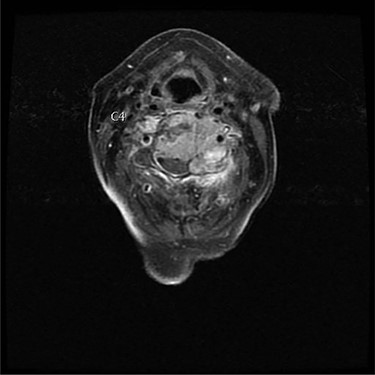

A 73-year-old female presented with neck pain and shooting pain down her left arm with associated paresthesias. Axial and sagittal imaging in the form of magnetic resonance imaging and computed tomography (CT) revealed a pathological fracture of C4, with extraosseous tumor extension from the vertebral body and a left lateral mass causing severe cervical spine stenosis (Figs 1 and 2). Thoracic imaging demonstrated a dorsal expansile osteolytic lesion at T8 with concomitant severe spinal canal stenosis. Following a standard work up of the lesion, it was determined that the patient had a renal cell carcinoma. A CT angiogram showed the cervical lesions received significant blood supply from the left vertebral artery.

Axial view of C4 tumor showing encasement of left vertebral artery.